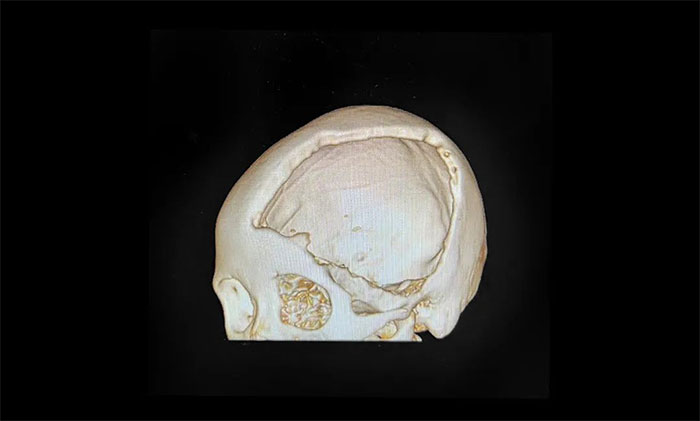

▲ 左侧颅骨大面积缺损

于耀宇主任解释道,颅骨缺损不仅非常影响外观,还会干扰颅内正常的血液循环和脑脊液循环,影响神经功能正常运行,甚至可能造成严重的神经功能障碍。

一般情况下,开颅手术3-6个月左右,就可考虑颅骨修补手术。及时修补,不仅可恢复颅骨的完整性,保护脑组织,避免“二次伤害”,增强患者安全感,而且可有效固定颅腔内容积,稳定大脑的外环境,避免颅骨缺损造成的脑组织变形、移位,有利于脑功能进一步恢复。

王女士虽恢复良好,但颅骨缺损较为严重(13cm*13cm),已影响到了正常生活。经评估,手术指征明显,无手术禁忌。在征得家属同意的情况后,于耀宇主任团队为她进行了颅骨钛板修补手术。手术过程顺利,术后安返监护病房。